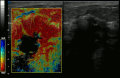

Elastography shows stiff cancer tissue on ultrasound imaging.

Ultrasound image shows irregularly shaped mass of breast cancer.